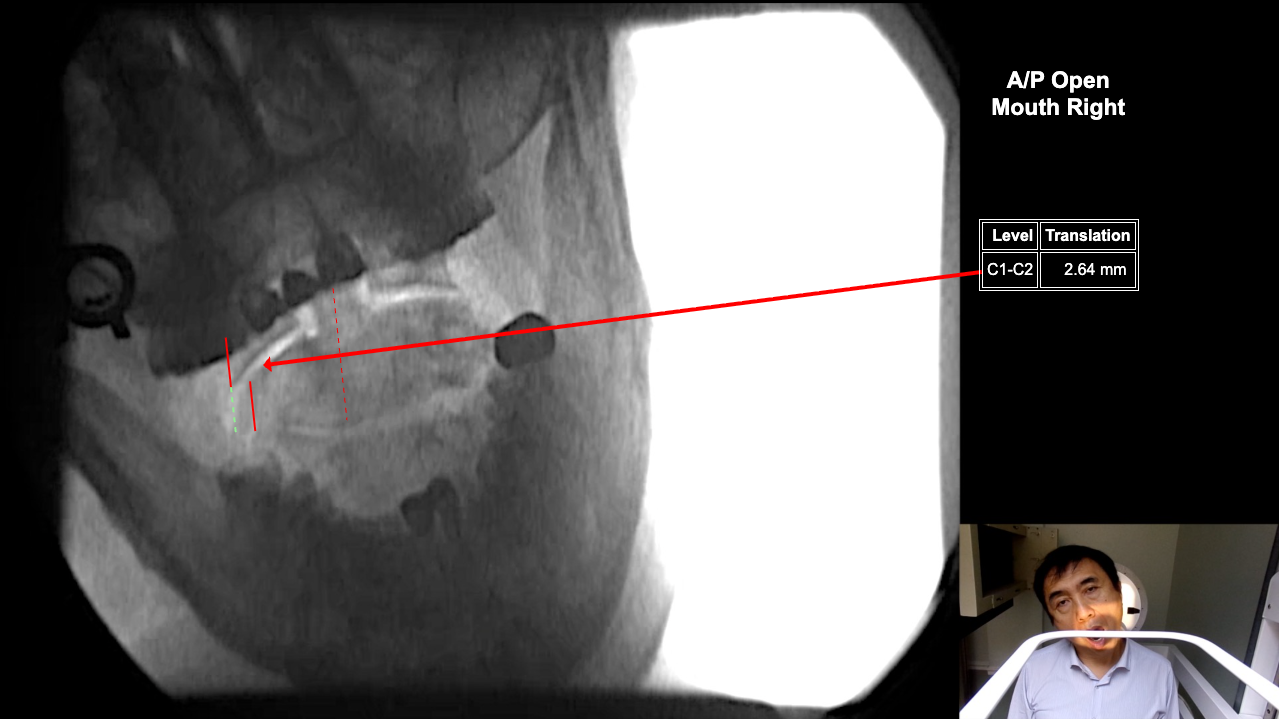

Image 2